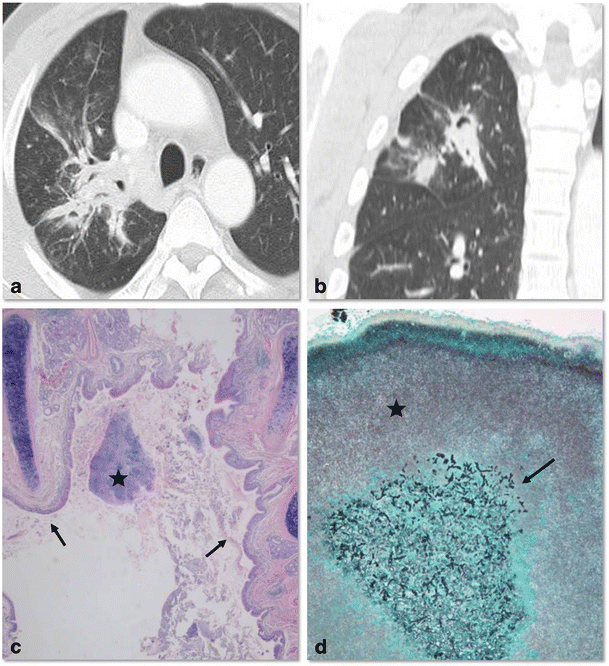

Actinomyces has a tendency to colonise devitalised tissue [15]. Actinomyces spp. colonise in the dilated bronchi and exacerbate pre-existing bronchial inflammation and bronchiectasis. Previous infections resulting in lung destruction such as tuberculosis and bacterial infections predispose patients to actinomycosis (Fig. 5). Common co-pathogens for thoracic actinomycosis have been described as Actinobacillus actinomycetemcomitans, Staphylococci, Streptococci, Haemophilus spp. and Aspergillus [16, 17]. The pathogenesis of co-infection is a synergistic effect: oxygen deprivation due to other bacteria creates an anaerobic milieu in which actinomyces thrive (Fig. 6) [16]. CT features of the bronchiectatic form include localised areas of bronchiectasis, irregular bronchial wall thickening, and irregular peribronchial consolidation with or without abscess formation [12]. The parenchymal type and bronchiectatic form may occur simultaneously. It is sometimes difficult to differentiate cystic bronchiectasis from central low attenuated necrotic areas of the parenchymal type (Fig. 7).

Co-infection of bronchiectatic actinomycosis with Aspergillus in a 52-year-old man. Chest CT scan in lung window setting obtained with an axial scan (a) and a coronal reformatted image (b) shows focal bronchiectatic changes with intraluminal nodules in the right upper lobe. The presumptive diagnosis was aspergilloma within bronchiectasis. Low-power photomicrography of the surgical specimen from the right upper lobe (c) (original magnification, ×20; haematoxylin-eosin stain) demonstrates an Actinomyces colony (star) within the ectatic bronchus (arrows). Medium-power photomicrograph (d) (original magnification, ×400; Gomori methenamine-silver stain) shows a nodule within bronchiectasis composed of central aggregation of Aspergillus (arrow) and surrounding Actinomyces colonies (star)